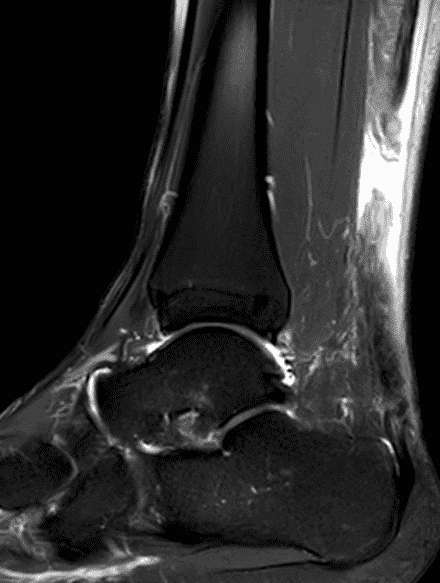

A 22 year-old male college football player presents with a “pop” and pain posterior to the right ankle during practice 1 week prior. He is unable to bear weight. Lateral radiograph (1A), sagittal fat-suppressed T2-weighted (1B), sagittal T1-weighted (1C), and transverse fat-suppressed T2-weighted images are provided. What is your diagnosis? What MRI findings affect clinical management decisions?

Figure 2: Complete Achilles tendon rupture. (2A) The lateral radiograph shows a thick and indistinct proximal Achilles tendon contour (arrows). (2B) A fat-suppressed T2-weighted image shows complete rupture of the tendon with a fluid-filled gap (yellow arrow) measuring 1.5 cm in length, located 10 cm cranial to the tendon insertion (blue arrow) and just distal to the edematous myotendinous junction (red arrow). The tear is superimposed on diffuse tendinosis. (2C) A sagittal T1-weighted image confirms the diffuse tendinosis. Fluid extends anteriorly into Kager’s fat pad (arrow) suggesting disruption of the anterior paratenon. (2D) A transverse fat-suppressed T2-weighted image through the proximal tendon shows no intact fibers (arrow), confirming the full-thickness rupture.

Acute, complete Achilles tendon rupture just distal to the myotendinous junction, superimposed on diffuse tendinosis.